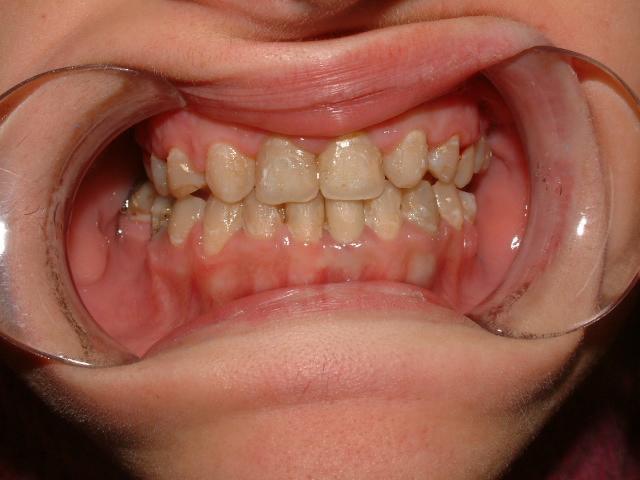

1η περίπτωση

Αρχική οδοντοσκελετική κατάσταση παιδιού με προγναθισμό άνω γνάθου και έντονη οριζόντια πρόταξη άνω τομέων Η σημασία της στοματικής υγιεινής και ορθοδοντικής

027 Αμέσως μετά το τέλος της ορθοδοντικής θεραπείας. Οι αλλαγές στην οδοντική του σύγκλειση αλλά και στο πρόσωπο είναι εμφανείς 15 χρόνια μετά την αρχική περάτωση της θεραπείας, το αποτέλεσμα παραμένει σταθερό και ο ασθενής απέκτησε ένα υγιές και αρμονικό χαμόγελο και πρόσωπο. Η σημασία της στοματικής υγιεινής και ορθοδοντικής πρόληψης